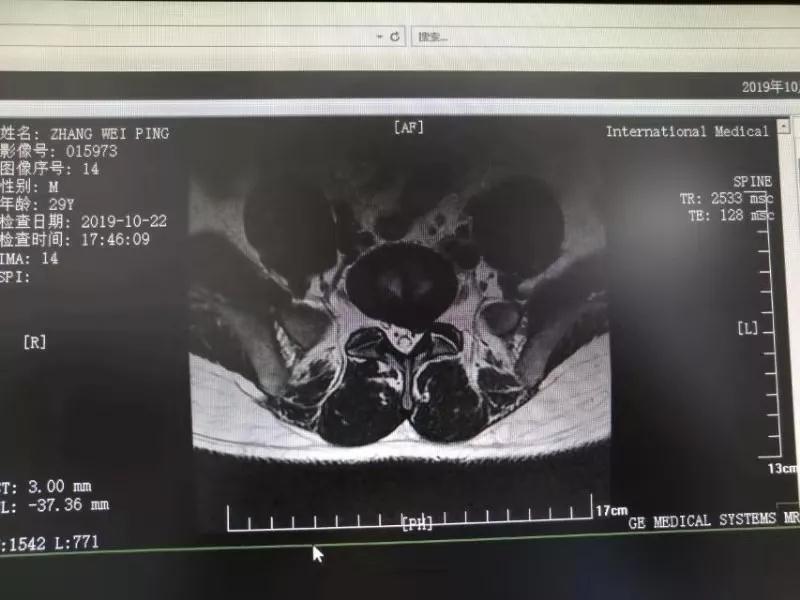

10月25日,29歲的患者小張了解到西安國際醫(yī)學中心骨科醫(yī)院專家云集,一大早便在家人的陪同下,來到西安國際醫(yī)學中心骨科醫(yī)院就診?!拔已闯掷m(xù)2年多,最近感冒后腰痛癥狀明顯加重了?!毙埫媛犊喑?,因為長期腰痛、左下肢放射性疼痛,她晚上睡覺不能平躺,經常疼得睡不著,需要口服止痛藥物才能有所緩解。走路走不了多遠就開始腿抽的疼,嚴重影響到工作和生活。

結合患者的檢查以及年齡情況,王自立副院長推薦讓專門研究椎間孔鏡技術王雄勛主任給小張做微創(chuàng)的椎間孔鏡手術。該手術創(chuàng)傷很小,不影響脊柱的穩(wěn)定性,尤其適合于椎間盤突出的年輕患者,懷著對骨科醫(yī)院專家的信任,小張與家人商議后,接受手術治療。